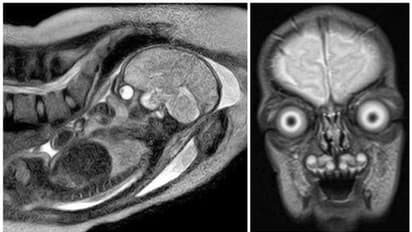

ഗര്ഭാശയത്തിന്റെ എംആര്ഐ സ്കാനിംഗുകള് അത്ര സാധാരണമല്ല. അവ അൾട്രാസൗണ്ട് സ്കാനിംഗിൽ നിന്നും വ്യത്യസ്തമാണ്. അതിനാല് തന്നെ അമ്മയ്ക്കോ ഗര്ഭസ്ഥ ശിശുവിനോ ആവശ്യമാണെങ്കില് മാത്രമേ എംആര്ഐ സ്കാനിംഗ് ചെയ്യുകയൊള്ളൂ. എന്നാല്, ഗര്ഭപിണ്ഡങ്ങളിലെ കഴുത്ത്, തൊറാസിക്, വയറ്., നട്ടെല്ല് എന്നിവയുടെ വൈകല്യങ്ങൾ നിർവചിക്കാനും കണ്ടെത്താനും അവയ്ക്ക് കഴിയുമെന്ന് ഗ്രേറ്റ് ഓർക്കണ്ട് സ്ട്രീറ്റ് ഹോസ്പിറ്റല് നിര്ദ്ദേശിക്കുന്നു. എംആര്ഐ സ്കാനിംഗ് ചെയ്താല് ഗര്ഭപിണ്ഡത്തിന്റെ തത് സമയത്തെ വളര്ച്ചയുടെ ചിത്രം ലഭിക്കുന്നു. കറുപ്പിലും വെളുപ്പിലുമുള്ള ചിത്രങ്ങളായിരിക്കും ഇത്തരം സ്കാനിംഗുകളില് ലഭിക്കുക. എന്നാല് ഇത്തരം ചിത്രങ്ങള് നമ്മുടെ ചിന്തയ്ക്കും അപ്പുറത്തുള്ള ഒരു കാഴ്ചയാകും സമ്മാനിക്കുക.

2021 ല് ഇത്തരത്തില് ഒരു ചിത്രം സാമൂഹിക മാധ്യമങ്ങളില് പങ്കുവയ്ക്കപ്പെട്ടിരുന്നു. സമാനമായ ചിത്രങ്ങള് കഴിഞ്ഞ ദിവസം സാമൂഹിക മാധ്യമങ്ങളില് വീണ്ടും വൈറലായി. ഈ ചിത്രങ്ങള്, ഗര്ഭപാത്രത്തിലുള്ള മനുഷ്യ ശിശുവിനെ കുറിച്ചുള്ള നമ്മുടെ ധാരണകളെ തകിടം മറിക്കുന്നവയാണ്. 2021-ൽ ഹാർവാർഡ് മെഡിക്കൽ സ്കൂളിന്റെ പിന്തുണയോടെ നടന്ന പ്രോജക്റ്റിന് പിന്നാലെയാണ് ഇത്തരം ചിത്രങ്ങള് സാമൂഹിക മാധ്യമങ്ങളില് പങ്കുവയ്ക്കപ്പെട്ടത്. ചിത്രങ്ങള് കണ്ട നെറ്റിസണ്സില് മിക്കവരും ചിത്രങ്ങള് കണ്ടപ്പോള് തങ്ങള്ക്കുണ്ടായ ആശങ്കകള് പങ്കുവച്ചു. ചിത്രങ്ങള് കണ്ടാല് പിശാചുക്കളാണ് ജനിക്കാന് പോകുന്നതെന്ന് ആളുകള് ഭയക്കുമെന്നായിരുന്നു മിക്കവരും കുറിച്ചത്. ചിത്രങ്ങള് കാഴ്ചക്കാരില് പേടിസ്വപ്നങ്ങള് ഉണ്ടാക്കുമെന്ന് എഴുതിയവരും കുറവല്ല. ചിലര് അത്തരം ചില രൂപങ്ങള് കോമിക്ക് പുസ്തകങ്ങളില് കണ്ടിട്ടുണ്ടെന്ന് രേഖപ്പെടുത്തി.

റെഡ്ഡിറ്റ് എന്ന സാമൂഹിക മാധ്യമത്തില് ഈ ചിത്രങ്ങള് പങ്കുവയ്ക്കപ്പെട്ടപ്പോള് ഇത് ഭൂമിക്ക് പുറത്ത് നിന്നുള്ള ജീവികളാണെന്നായിരുന്നു ചിലര് കുറിപ്പെഴുതിയത്. ചിത്രങ്ങള് ടിം ബർട്ടണിന്റെ അന്യഗ്രഹ ജീവികളെക്കുറിച്ചുള്ള സിനിമകളില് നിന്നുള്ളവയാണെന്നായിരുന്നു ചിലര് എഴുതിയത്. മറ്റ് ചിലര് സാത്താന്റെ സന്തതികളെന്ന് കുറിച്ചു. ചിത്രങ്ങള് വ്യാപകമായി പ്രചരിപ്പിക്കപ്പെട്ടതോടെ Snopes എന്ന ഫാക്റ്റ് ചെക്ക് വെബ്സൈറ്റ് അവ യഥാര്ത്ഥ ചിത്രങ്ങളാണെന്ന് കണ്ടെത്തി റിപ്പോര്ട്ട് ചെയ്തു. പ്രായവുമായി ബന്ധപ്പെട്ട മസ്തിഷ്ക മാറ്റങ്ങൾ പഠിക്കാൻ എംആർഐ സാങ്കേതികവിദ്യ ഉപയോഗിക്കുന്നുവെന്ന് വിസ്കോൺസിൻ സർവകലാശാലയിലെ ഗവേഷകര് അറിയിച്ചതായും അവര് റിപ്പോര്ട്ട് ചെയ്തു. ട്വീറ്റിലെ രണ്ട് ചിത്രങ്ങള് നേരത്തെ ഹാര്വാര്ഡ് സര്വകലാശാല ഗവേഷകര് പങ്കുവച്ചതായും വെബ്സൈറ്റ് റിപ്പോര്ട്ട് ചെയ്തു.